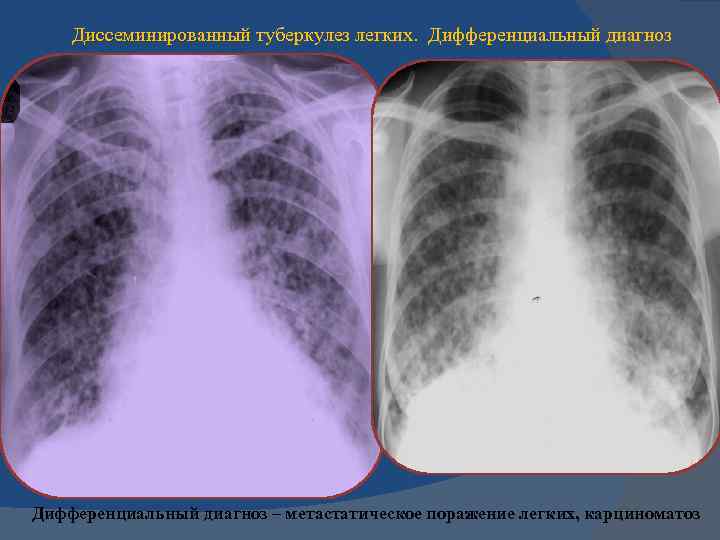

Рентгенологические изображения и синдромы патологии легких

Раздел: Кадры-подсказки